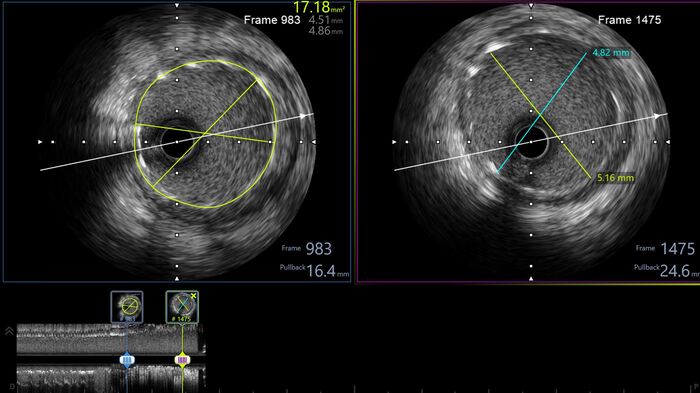

С учетом данных ВСУЗИ проводится сразу прямое (без предварительной предилатации баллоном) стентирование ПМЖА с покрытием ствола левой коронарной артерии.

Контроль ультразвуком: